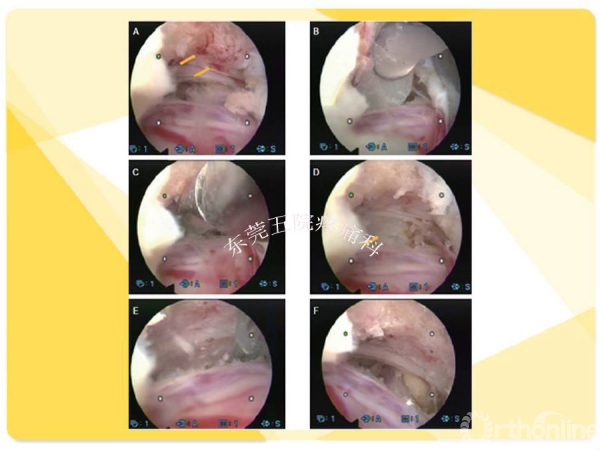

如何在椎间孔镜术前有效预防并发症的发生?如果不幸发生了该如何快速准确地处理?广东省东莞市第五人民医院疼痛科康健主任医师为大家分享了他的经验——